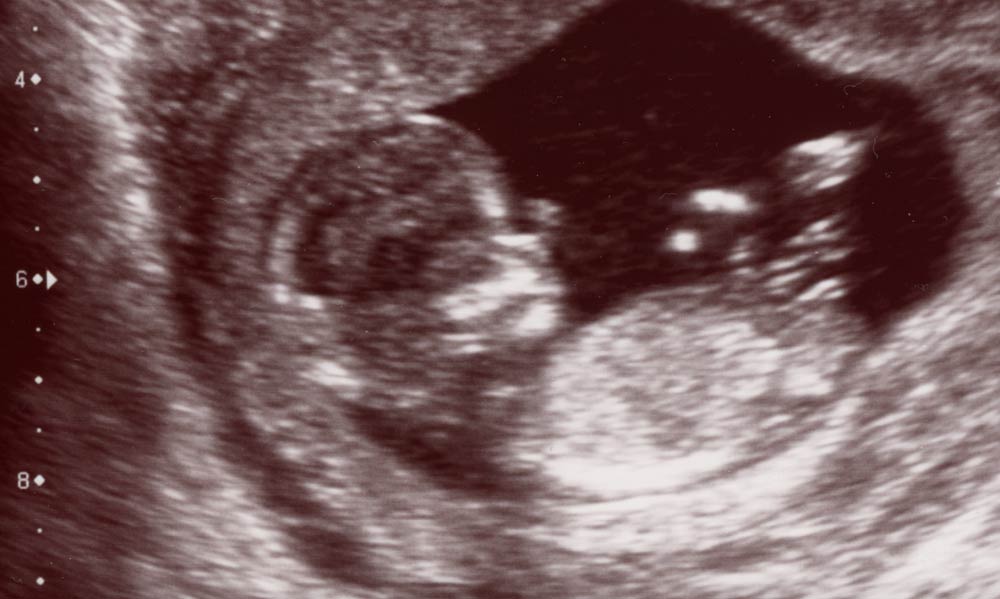

Second Scan

The second official viewing ( actually the third in our case ).

Blood was finally taken and the tests for Downs etc. were all classed as “low risk”  Its good to know even after last weeks excitement that things are going well for both Mrs and Junior Worrybomb.